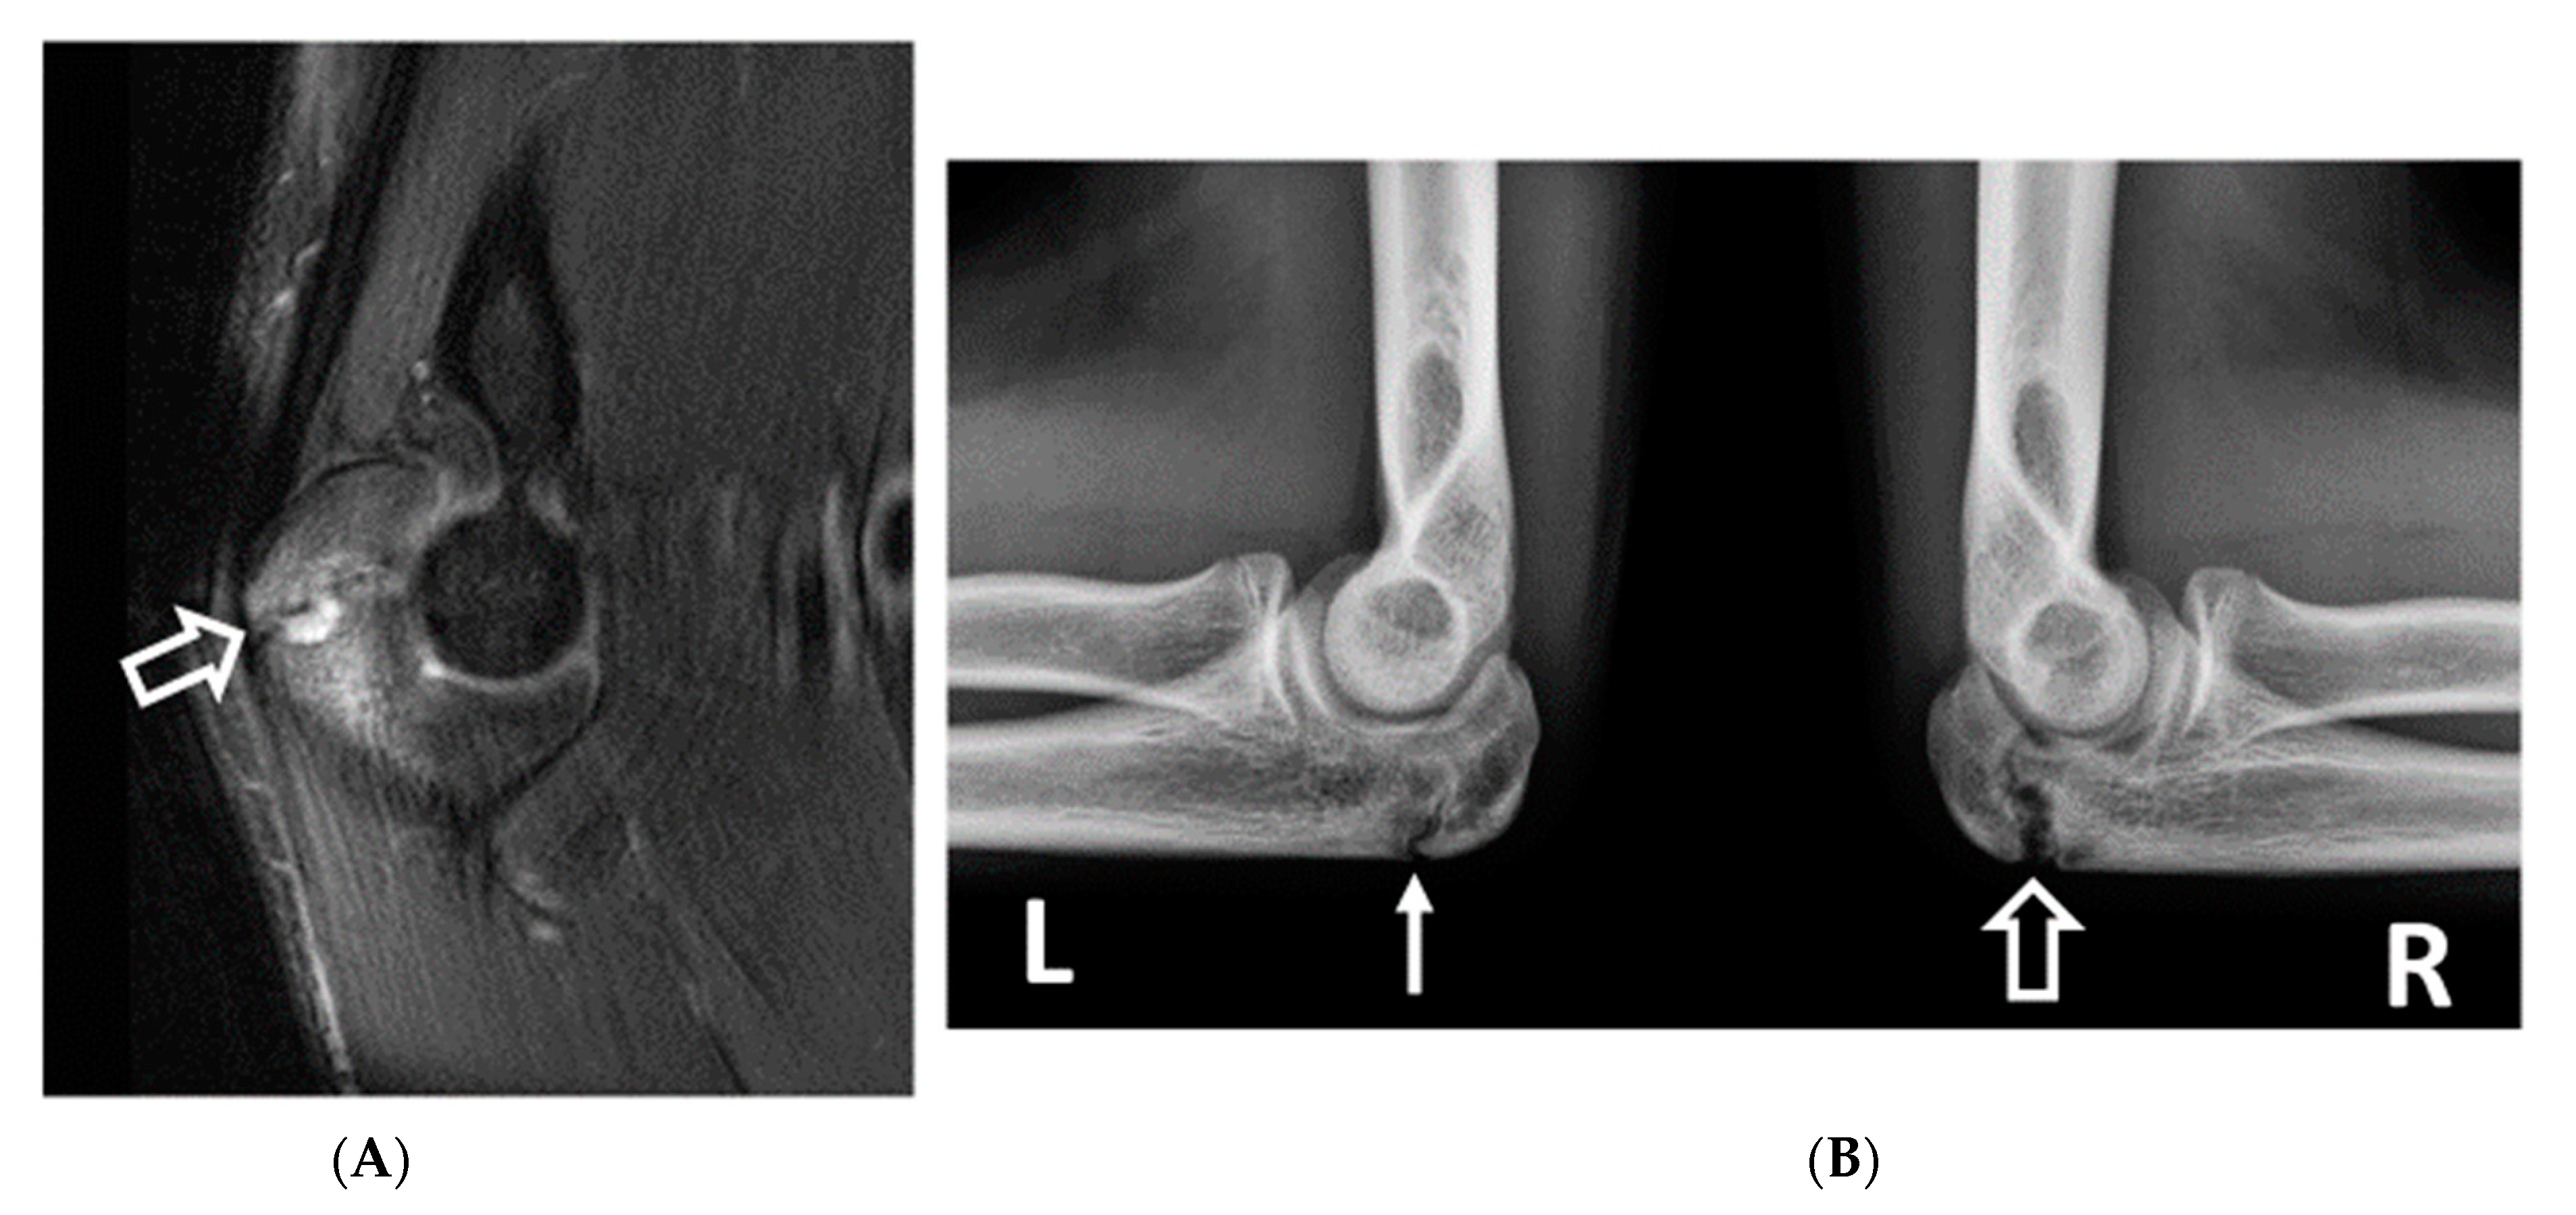

Figure 3.

A 12-year-old right-hand-dominant male baseball pitcher who developed acute medial elbow pain during a pitching lesson. (A) AP radiograph demonstrates an acute avulsion fracture of the medial epicondylar apophysis (arrow). (B) Coronal fat-saturated T2-weighted image demonstrates an acute avulsion fracture of the medial epicondylar apophysis (arrow). The anterior band of the ulnar collateral ligament remains intact (arrowhead).

Osseous abnormalities resulting from valgus extension overload were seen more frequently in younger athletes. Medial epicondylar apophysitis and acute apophyseal avulsion injuries from medial tension overload were only observed in athletes in subgroup 1 (Figure 3), although evidence of chronic avulsion injury was seen in the older age groups. Osseous findings from radiocapitellar overload were also seen most frequently in athletes in subgroup 1 (Figure 4), whereas posterior humeroulnar chondral injuries occurred with greatest frequency in subgroup 2.